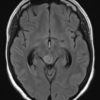

Cavernoma

» Thông tin: Nam giới – 30 tuổi.

» Lâm sàng: Đau đầu.